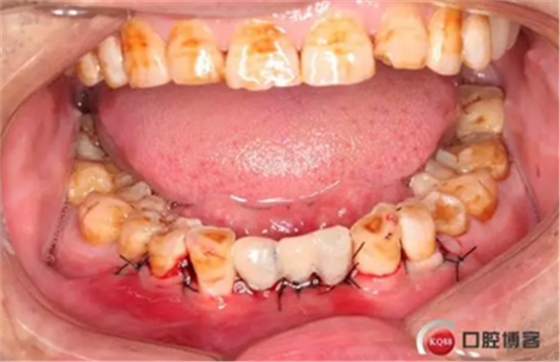

下圖是術(shù)后照片 治療過程 術(shù)前測(cè)量上下牙長(zhǎng)度比例,確定水激光冠延長(zhǎng)深度約3mm,拔除31、41,在術(shù)區(qū)減低牙槽嵴高度,32、42位點(diǎn)種植MINI型一段式種植體,使用臨時(shí)愈合帽行暫時(shí)性修復(fù)。

治療前后照片顯示患者上下臨床牙冠比例協(xié)調(diào),患者對(duì)臨時(shí)修復(fù)體效果十分滿意。當(dāng)然有待后期愈合及長(zhǎng)期的臨床隨訪,以觀察遠(yuǎn)期臨床效果。將水激光應(yīng)用臨床冠延長(zhǎng),有利于精準(zhǔn)去除骨量,利于術(shù)后愈合。而MINI型一段式種植體滿足骨寬度不足,及臨時(shí)修復(fù)打下堅(jiān)實(shí)基礎(chǔ)。